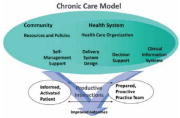

| 13:11, 21 בספטמבר 2023 | CCM1.png (קובץ) |  |

350 קילו־בייטים | Motyk | 1 | |